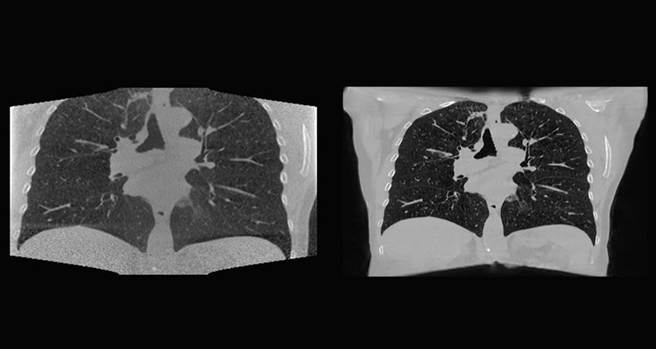

NKI过去使用低解析度影像来训练AI模型。由于NVIDIA AI Enterprise可提供更高的记忆体容量,该单位的研究人员可以改用高解析度的影像进行训练,如此一来便有助于临床医生在病人每次接受治疗时,更精准地锁定肿瘤的大小和位置。

NKI的研究人员使用运行在HPE组合式软体系统HPE Synergy上的NVIDIA AI Enterprise来建立深度学习模型,结合巨量的2D及3D资料来源和AI,在每次进行放射治疗前精准地锁定肿瘤位置。